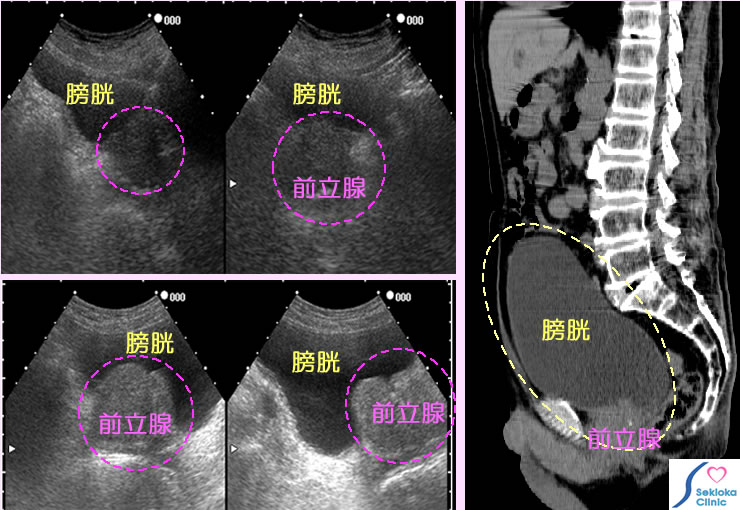

| 診断 | 超音波エコーで前立腺のサイズを計測。排尿後、膀胱内にどのくらい残尿があるかも計測。排尿障害が強く、長い場合は腎盂の拡張がないかも調べます。添付画像の波線円内が前立腺です。上段の例は肥大例、下段は著明な肥大例(本来手術適応例)。右側の3次元CTの膀胱断面画像は 排尿障害で来院し、膀胱の著しい膨満を認めた例。本例は薬剤服用で 2日目から改善、残尿は消失。 |